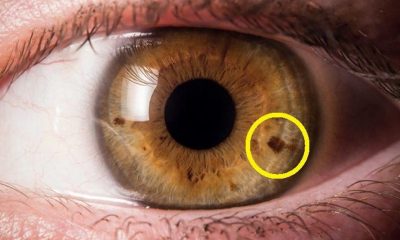

Κοιτάξτε τα Μάτια σας στον Καθρέφτη. Μήπως έχετε ΑΥΤΑ τα Στίγματα; Δείτε ΤΙ αποκαλύπτουν για την Υγεία σας.

12 Μαρτίου 2019Μπορείς να καταλάβεις πολλά για το πώς νιώθει κάποιος κοιτώντας τα μάτια του. Αλλά γνωρίζατε όμως...